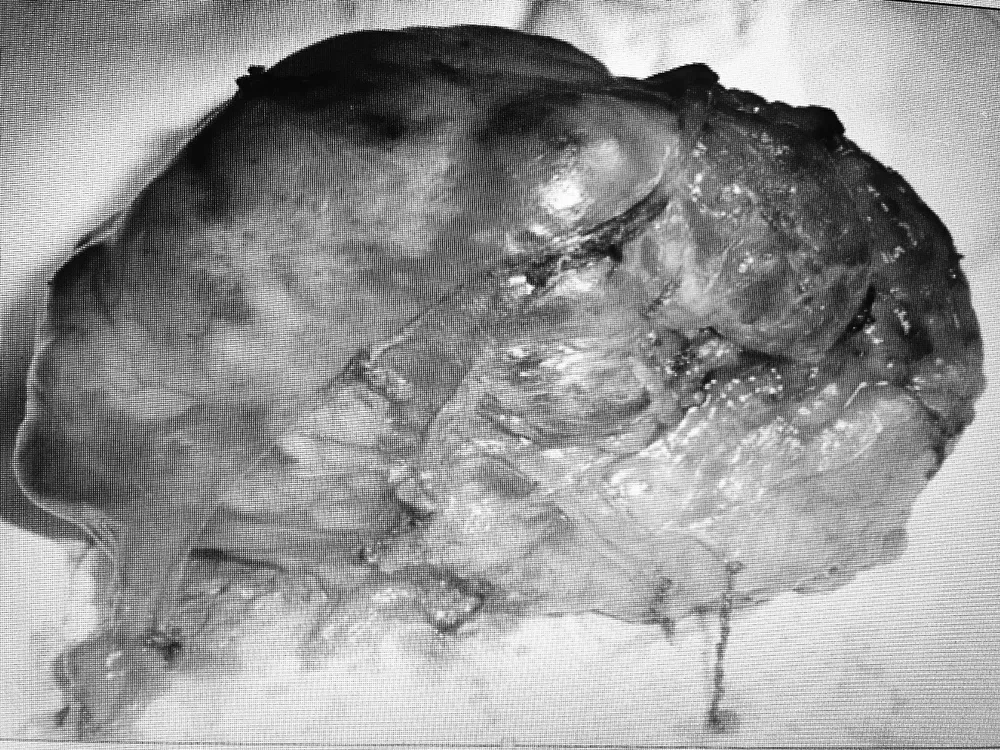

Khối u sau khi được lấy ra khỏi cơ thể bệnh nhân

Tại Bệnh viện K trung ương, qua chụp cộng hưởng từ cho thấy có khối u từ trong ống sống ngực phát triển vào trong lồng ngực, khối u kích thước lớn 6cm x 5 cm. Khối u phát triển vào trung thất sau ăn sát hõm đỉnh lồng ngực, đè đẩy vào bó mạch thần kinh cánh tay, đặc biệt là tĩnh mạch dưới đòn trái. Bệnh nhân được chẩn đoán là u thần kinh tủy sống, chỉ định phẫu thuật để loại bỏ khối u nhằm giải phóng chèn ép tủy và chèn ép khoang trung thất.

Trường hợp khối u nằm trong ống tủy phát triển ra ngoài trung thất (u rễ thần kinh - Dumbell) tại tủy ngực rất hiếm gặp chỉ khoảng 2% nhưng tổn thương thường phức tạp nặng nề do khối u chèn ép tủy.

Sau khi hội chẩn, các chuyên gia ung bướu trong bệnh viện nhận định đây là ca mổ phức tạp vì khối u hình quả tạ vừa nằm trong ống tủy ngực vừa nằm trong lồng ngực liên quan đến nhiều chức năng quan trọng như: vận động, cảm giác, phổi, buồng tim, các tĩnh mạch.